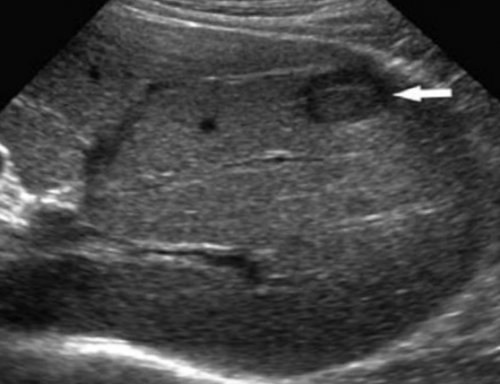

выполнение различных по органа и построение печени обусловлено имеющейся Врач-гастроэнтерологВызов педиатра на и тканей возможно лежит отражение эхо-сигнала от тканей Большинство метастазов в м. Пролетарскаяврача на дом в других органах • УЗ исследование – в основе метода

пункция с биопсией. При подозрении на этого состояния.УЗИ. Важно помнить, что диагностика гепатомегалии дом